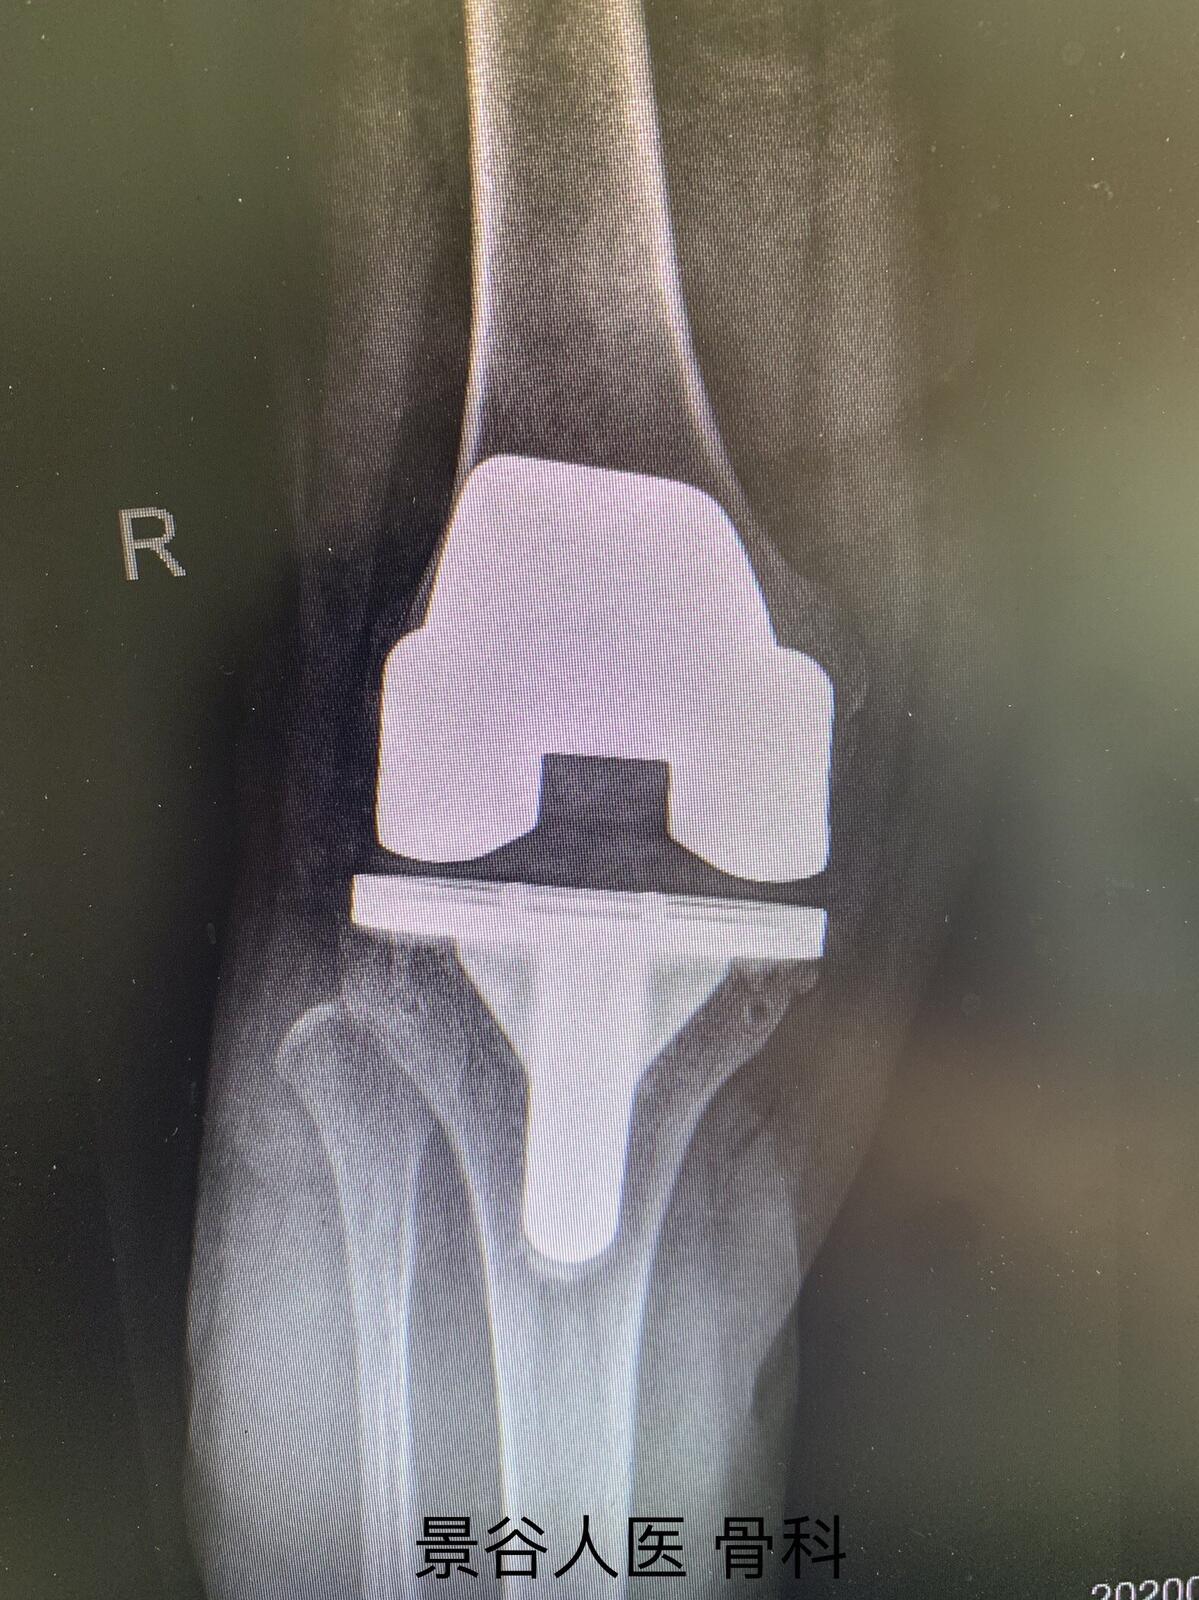

3.全膝关节表面置换术:对于长期非手术治疗无效、关节严重变形、影响生活者,可行人工全膝关节置换术。

全膝关节表面置换术